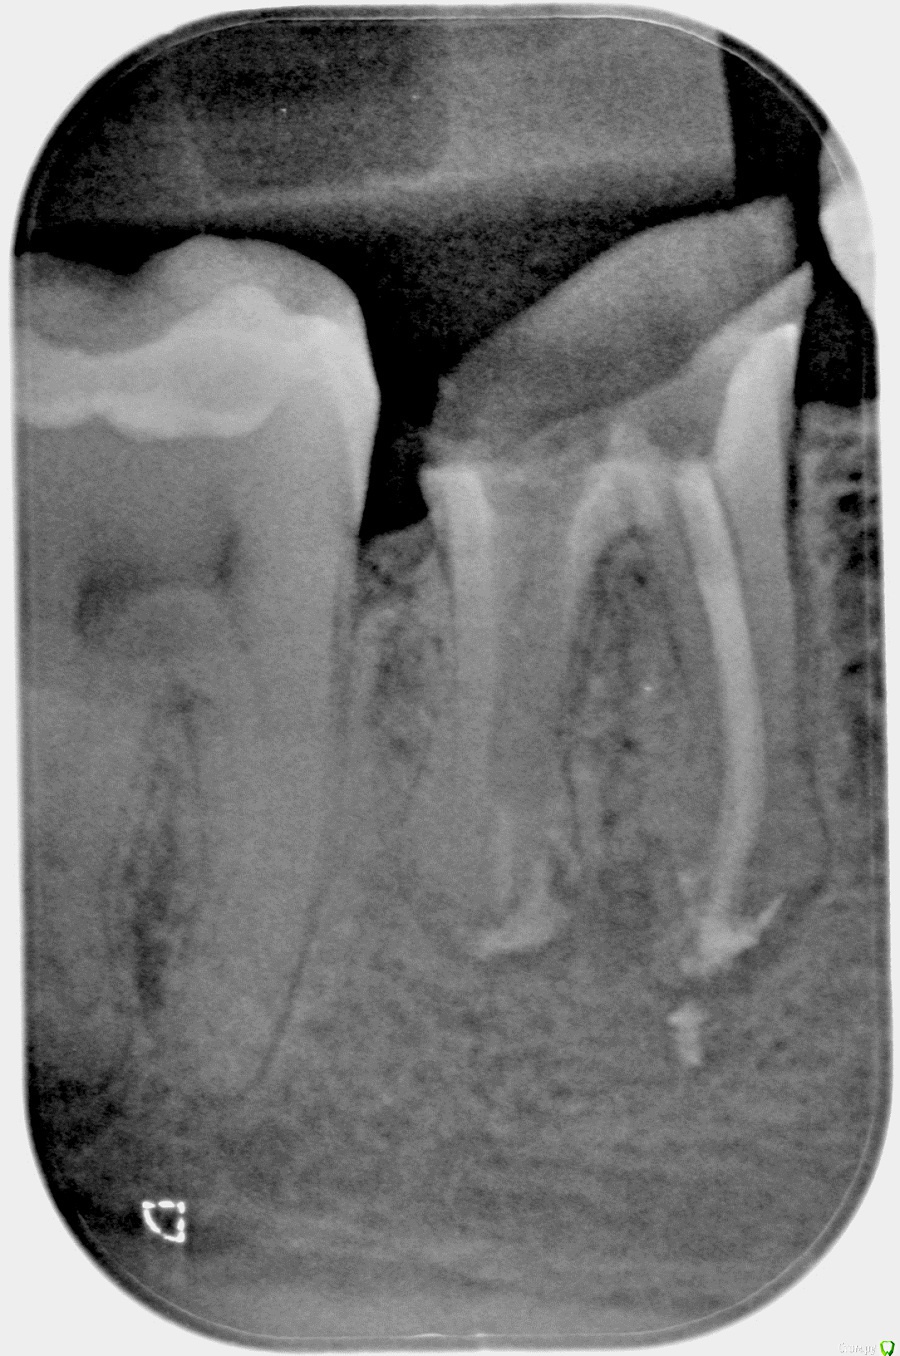

na_natali Опубликовано 5 июня, 2018 Поделиться Опубликовано 5 июня, 2018 Добрый день. Есть депульпированный зуб, обточенный под вкладку. В процессе подготовки зуба предположительно был перфорирован корень. Под временной пломбой зуб начал болеть, после открытия в канале обнаружена кровь.Предпринята попытка закрыть перфорацию. На снимке перфорация не визуализируется, место найти не удалось.Возможно, что зуб был поврежден в процессе подготовки, но непосредственно перфорации не было, а позже корень в истонченном месте треснул от нагрузки.На данный момент канал закрыт реставрирующим материалом и временной пломбой. Боль значительно уменьшилась, но присутствует при накусывании (слабовыраженная). Периодически появляются ноющие боли.Зуб закрыт на месяц - полтора, далее по ситуации. Если по истечении этого периода болей не будет,есть ли смысл ставить на него коронку? Мнения врачей разделились.Часть говорит что проще удалить и поставить имплант. Часть что установка коронки таки возможна.Снимки "до" и "после" прилагаю.Какие будут мнения? Ссылка на комментарий